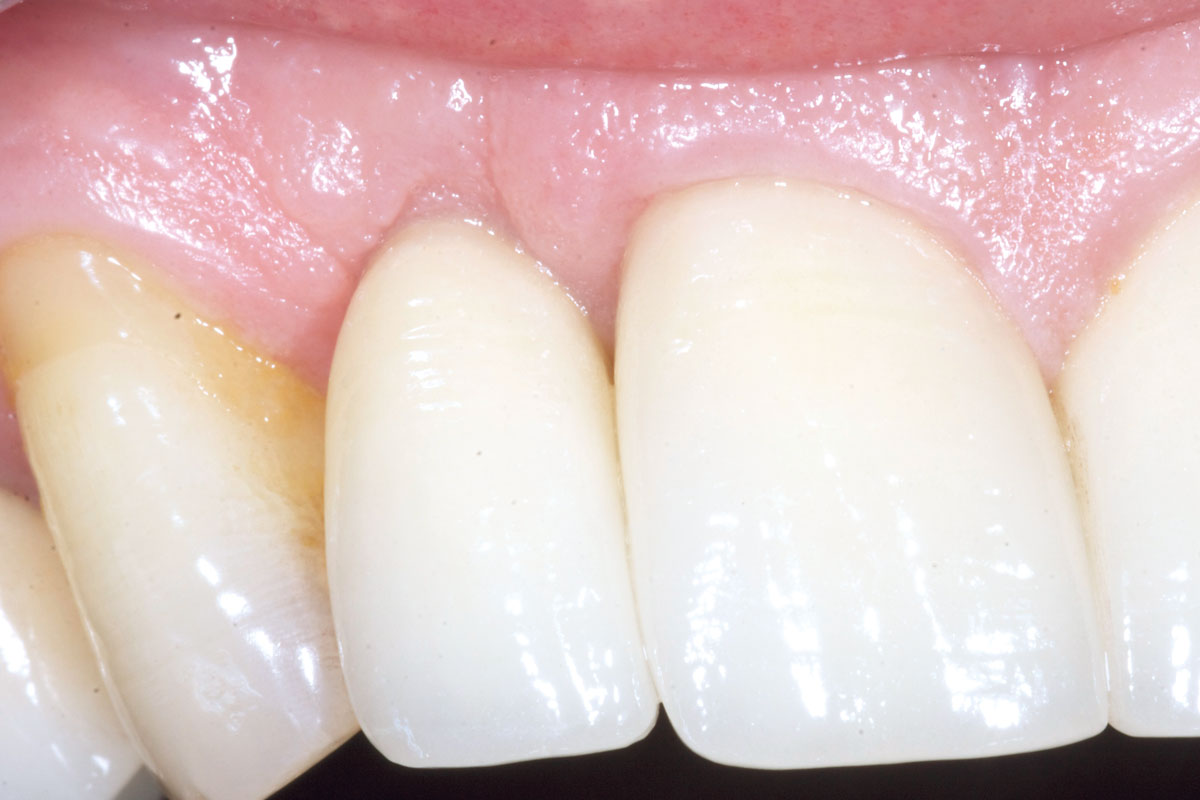

19/19 - Final result 1 year after implant placementBone augementation with maxresorb® - Dr. R. Cutts